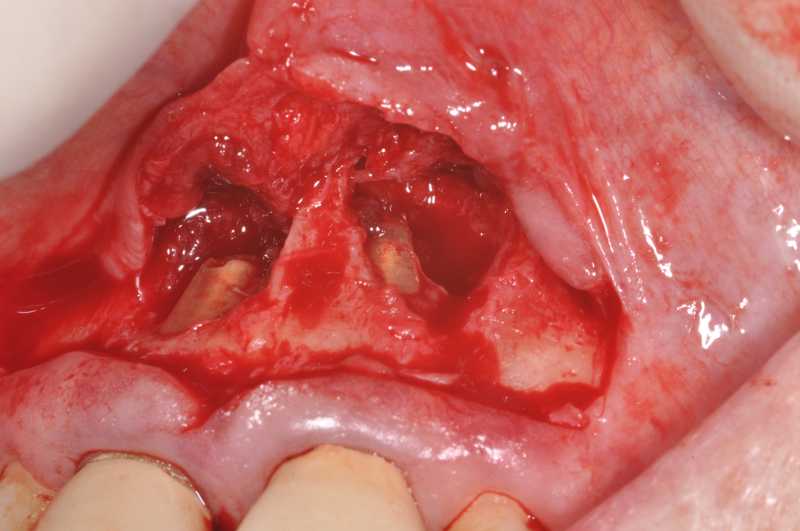

Inicio Especialidades Endodontia